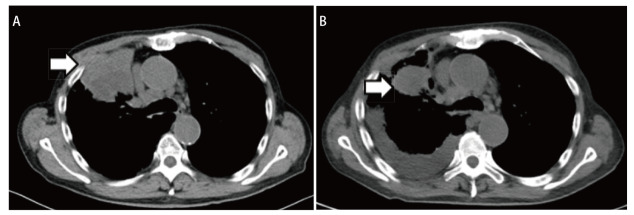

Programmed cell death 1 (PD-1) inhibitor therapy for lung adenocarcinoma may induce rare but severe hematologic adverse events, including severe anemia. Although glucocorticoids are recommended for managing immune-related adverse events, therapeutic experience with PD-1 inhibitor-induced severe anemia remains limited, and its efficacy and safety have not been fully validated. This article reports a case of advanced lung adenocarcinoma in which severe anemia developed following combination therapy with chemotherapy and PD-1 inhibitor. After comprehensive evaluation, the patient was diagnosed with anemia of inflammation (AI) and achieved significant hemoglobin recovery following high-dose glucocorticoid treatment. These findings may provide new insights into the recognition and management of this rare hematologic toxicity in clinical practice.